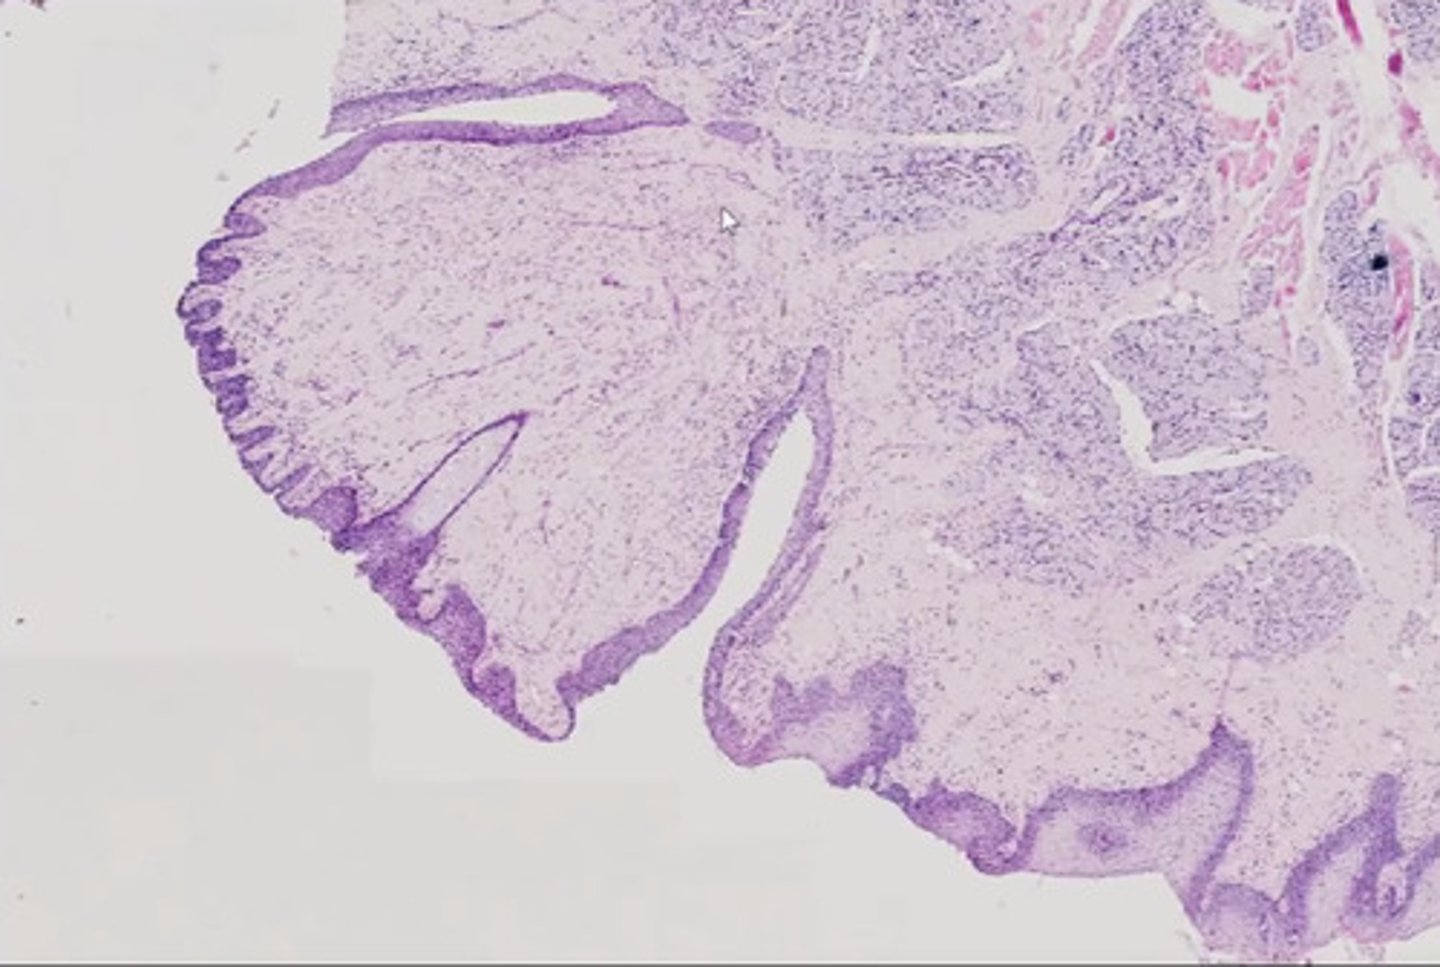

Wyrostek robaczkowy (H+E)

Język - migdałek językowy (H+E)